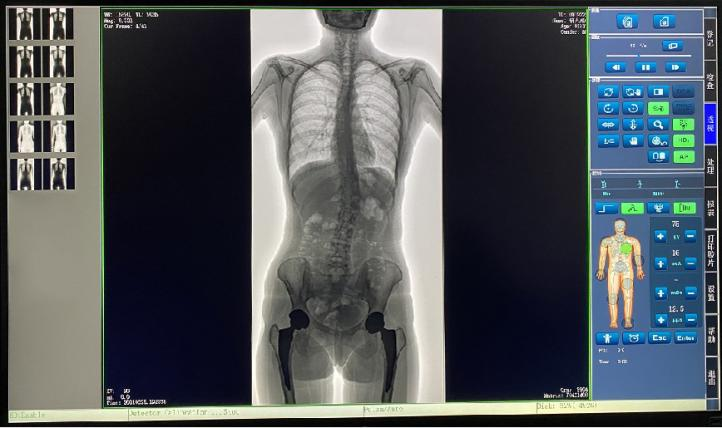

普愛醫療新推出一款動態平板DR-PLX8600,這款產品可攝影、可透視、可造影,臨床適用范圍廣泛,可滿足不同臨床拍攝需求。一體式的機架,擺位簡單快捷,不僅融合了市面上17英寸動態DR的所有功能,還有獨具特色的超大動態視野范圍,給臨床應用帶來醫療診斷價值,降低醫院設備投入成本,獲得更大收益。

1.專為大視野臨床應用打造的平板動態DR,圖像不拼接,有效簡化影像科室檢查流程,提高診斷精度,降低患者吸收的輻射劑量。

2.解決了拼接圖像存在密度不均勻,拼接處圖像配準和放大效應等問題,輻射劑量小。